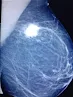

Breast cancer has become a common health problem these days. It is often heard that someone is suffering from this problem. We don't understand when and how we get infected. Or if someone can understand, but we keep quiet in shame.

According to medical oncologists, mammography is a

special type of X-ray of the breast. Very little radiation is used in this

test.

Several studies have shown that women over 50 years of

age benefit from regular breast mammography. Therefore, internationally

mammography is considered as a powerful means of breast cancer screening.

abnormal changes in the breast or if there is a lump or lump in the breast,

calcification or accumulation of calcium metal can be understood through this

test. Cancer is suspected based on the presence of wheals, fine calcium

granules, pattern of format and many other factors. It is important to compare

previous mammograms with new mammograms.

When needs to further tests – suspicious areas are

indicated on the mammography film. However, it cannot be confirmed that cancer

has occurred. A biopsy of the suspicious area should be confirmed.